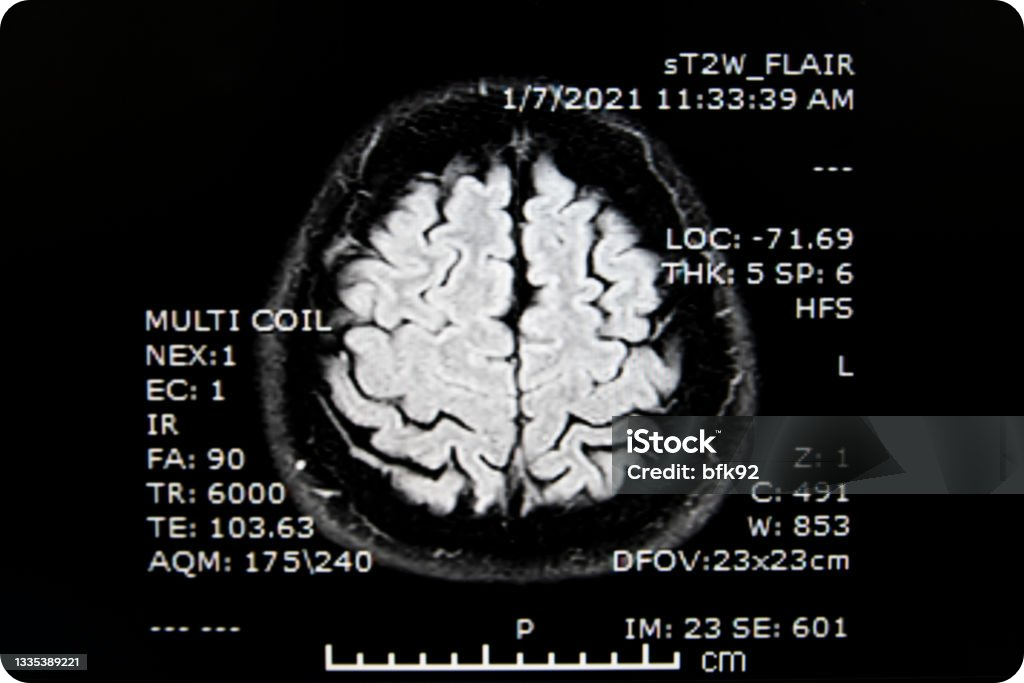

뇌혈관질환 MRI와 MRA진단.

- MRI : 뇌질환 상태를 진단하기 위한 영상.

- MRA : 뇌혈관 상태를 진단하기 위한 영상.